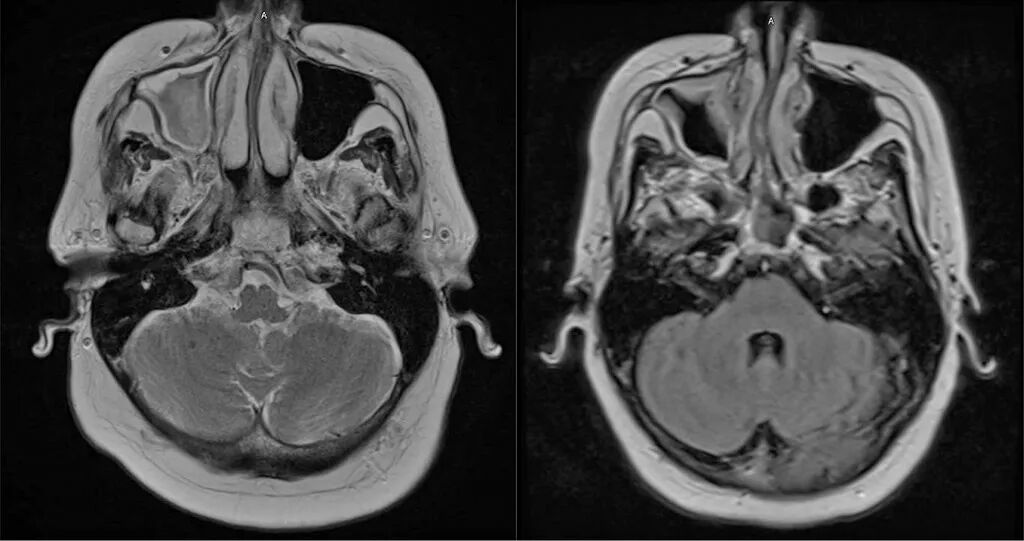

由于药物治疗未能缓解症状,患者接受了鼻窦手术;术后影像学检查证实病变改善(图1)。尽管如此,头痛仍然存在。

图1.左图:鼻窦手术前脑部磁共振成像显示副鼻窦疾病,以右侧上颌窦最为明显。右图:术后磁共振成像显示黏膜增厚有所改善。患者头痛症状未见变化。